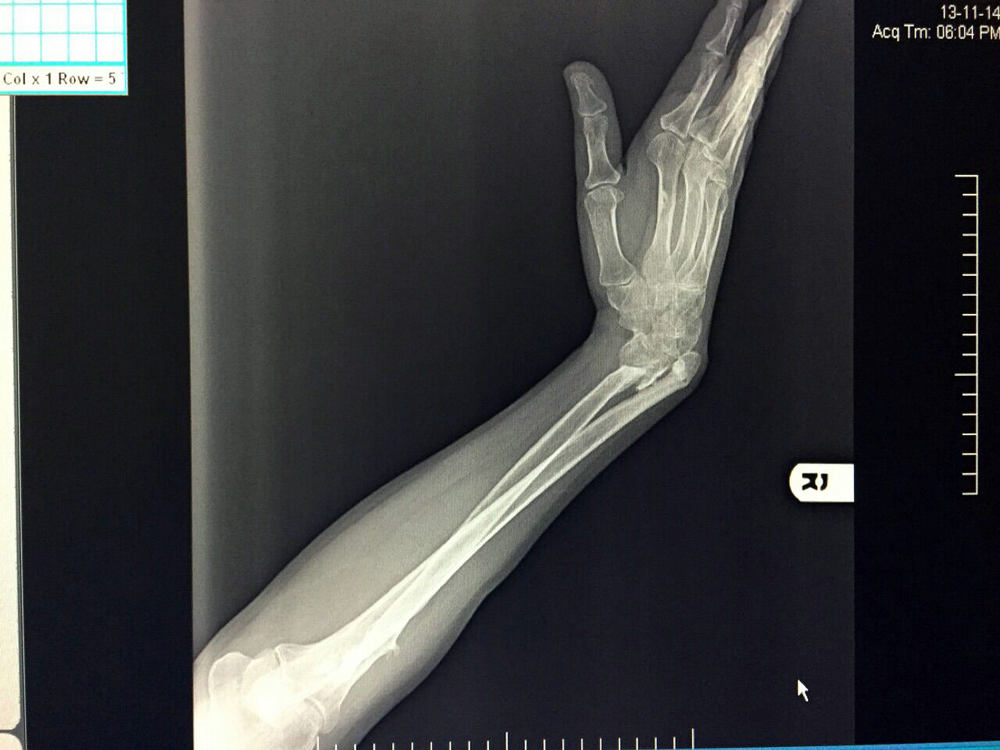

Wrist Deformity Correction